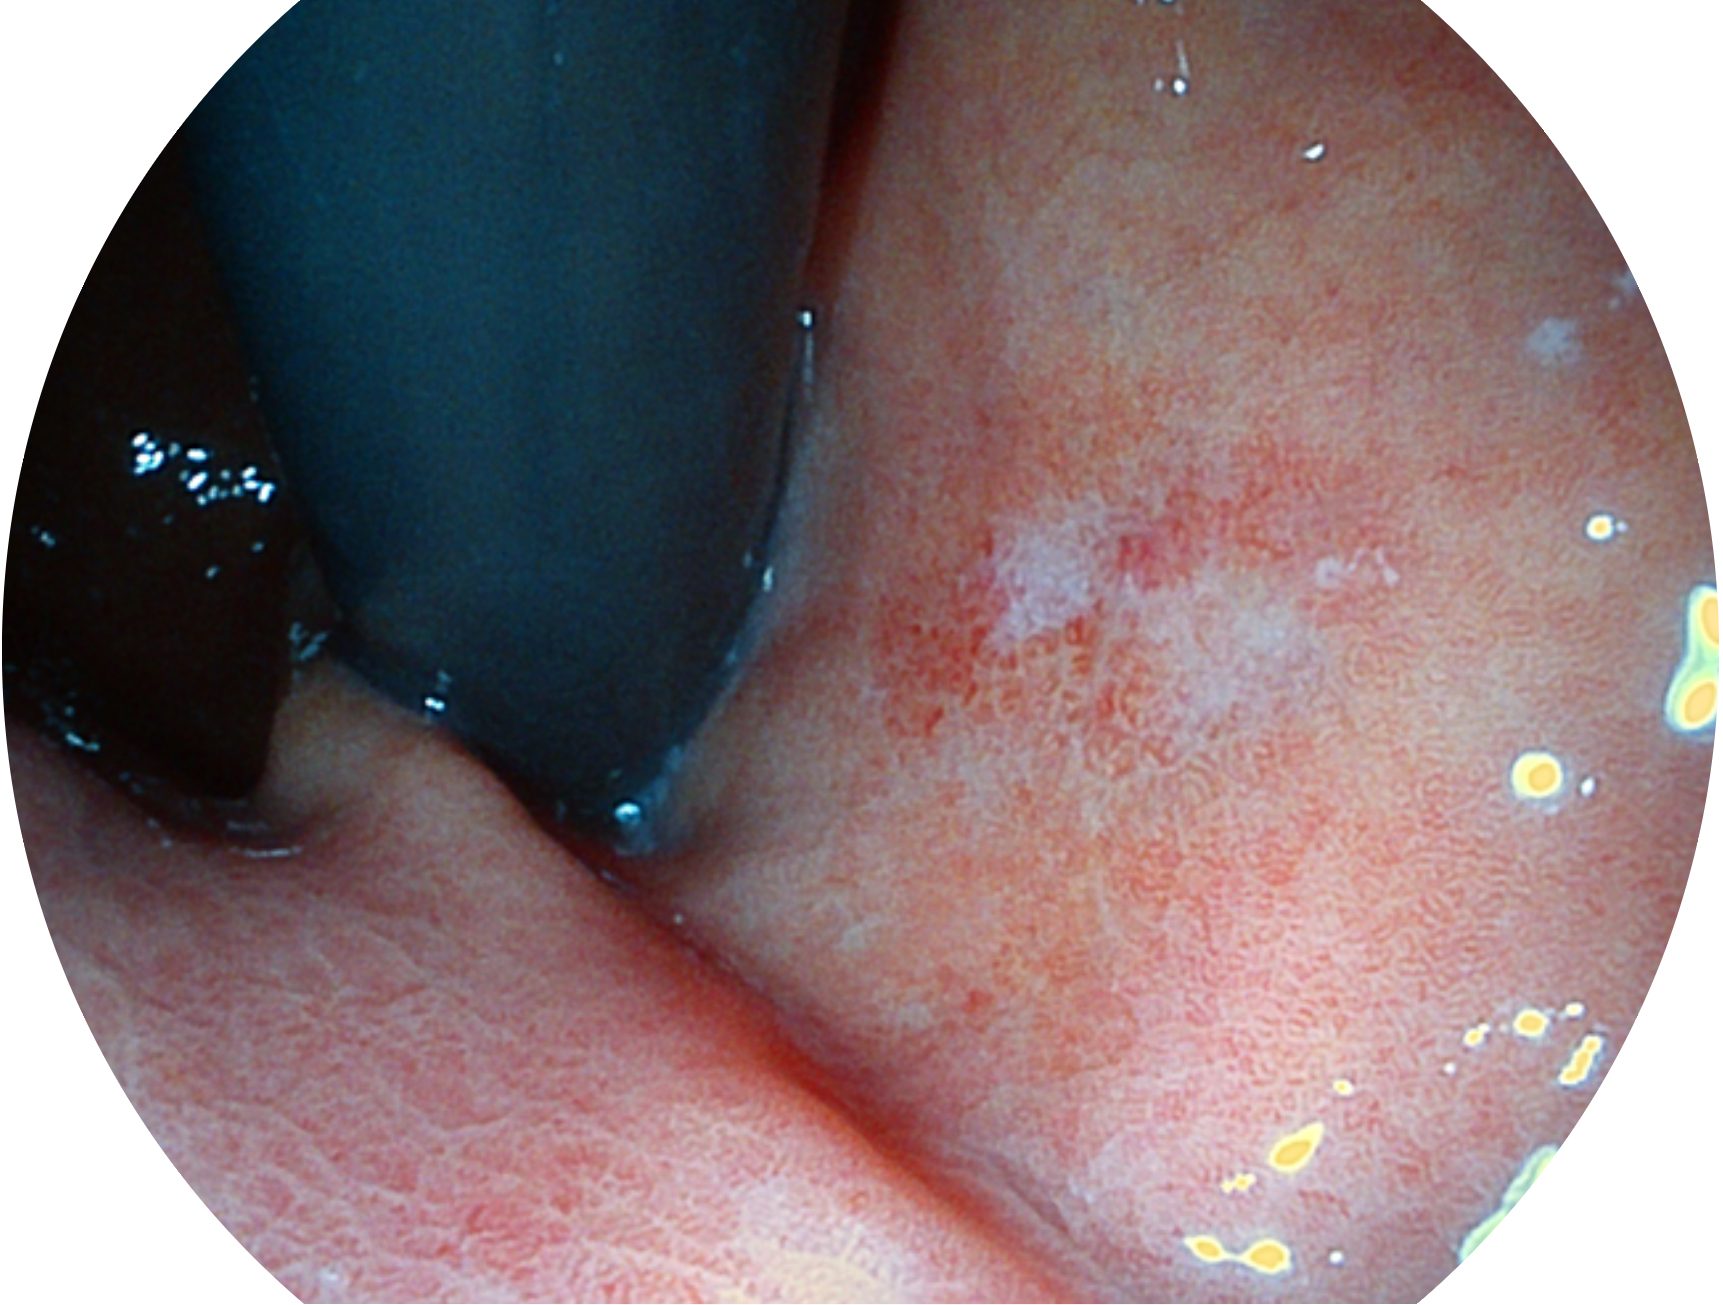

開立新開發(fā)的內(nèi)鏡染色技術(shù),主要是基于多波長(zhǎng)LED 光源的開發(fā),VLS-55Q 四波長(zhǎng)LED 光源是由四個(gè)不同顏色的LED光按照相應(yīng)照明模式所規(guī)定的特定發(fā)光比例進(jìn)行合束后形成,合束后形成的照明光的光譜由紅光、綠光、藍(lán)光及藍(lán)紫光這四個(gè)不同的波段范圍構(gòu)成。具有更高光譜自由度,通過(guò)光譜比例的控制,實(shí)現(xiàn)了聚譜成像技術(shù),英文全稱為“Spectral Focused Imaging, SFI”,縮寫為“SFI”和光電復(fù)合染色成像技術(shù),英文全稱為“Versatile Intelligent Staining Technology, VIST”,縮寫為“VIST”。